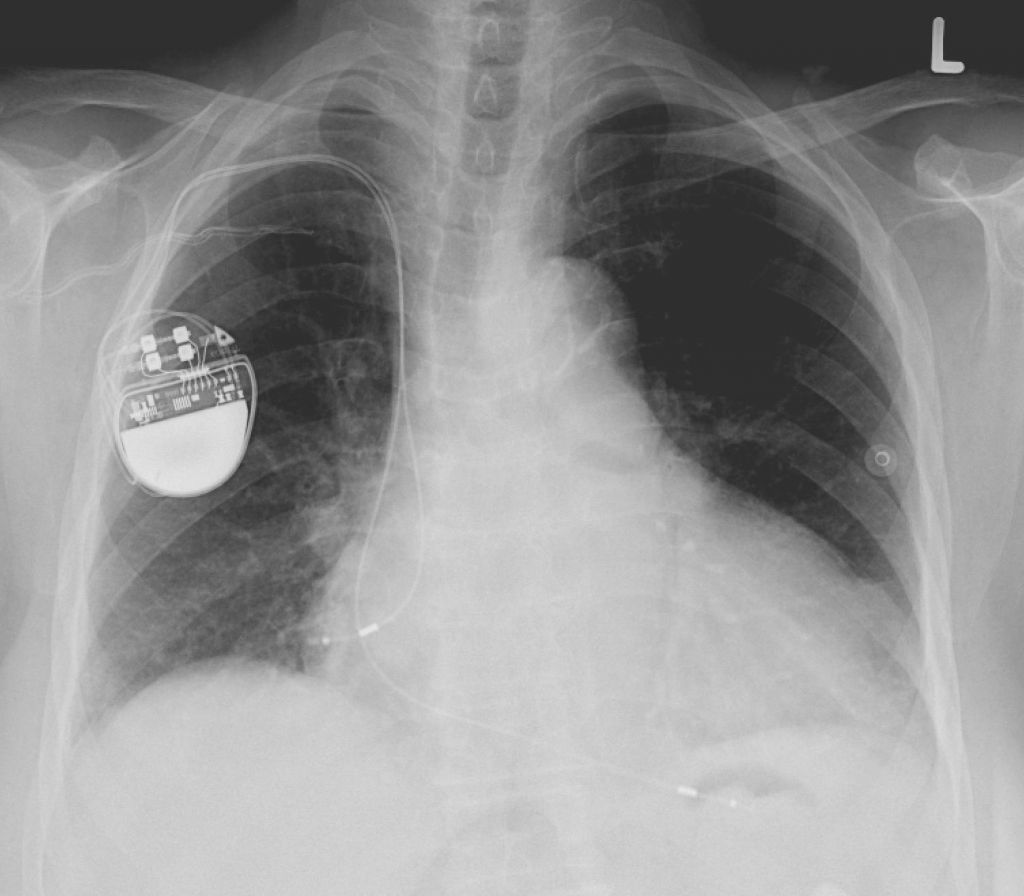

2Marcapasos

En una de las conferencias sobre seguridad informática más conocidas e importantes a nivel mundial, la Black Hat USA 2018, se hizo una conferencia llamada «Understanding and Exploiting Implanted Medical Devices«.

En ella se mostraban pruebas de concepto y técnicas para poder atacar a estos dispositivos como los marcapasos.

Algunos modelos de marcapasos israelíes, entre los que e encuentran casi medio millón de ellos, estaban en la lista negra. Estos dispositivos tenían como novedad conectarse a una pantalla de forma remota para poder monitorizar al paciente. Pero esa posibilidad de ver esos datos biomédicos también hacen que cualquier persona cercana pueda aprovechar algunas debilidades para realizar un ataque y hacer que funcione a un ritmo inapropiado produciendo arritmias o agotando la batería de forma precipitada. Es decir, se podría poner en riesgo la vida del paciente.